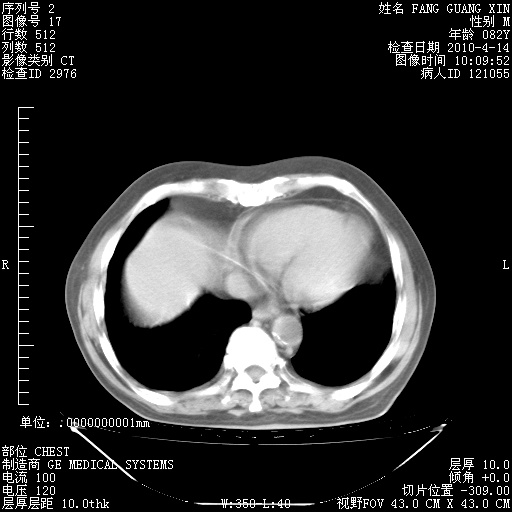

楼主| 发表于 2010-4-28 16:59 | 显示全部楼层

4月28日肺部CT——再次出现类似去年5月9日——透光度降低,(影像科认为)“间质性”改变。

1221483 1 .bmp

1221483 2 .bmp

1221483 3 .bmp

1221483 4 .bmp

1221483 5 .bmp